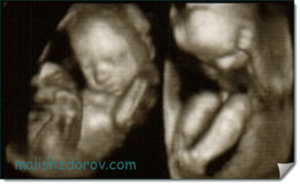

В этот период тело ребенка выглядит полностью сформированным, как показано на фото, но остается слишком худым, поскольку накопление подкожного жира только начинается. Дерма пока остается красной и морщинистой, на головке появляется пушок.

Во время УЗИ мама может увидеть, что:

- конечности стали пропорциональными;

- на пальцах есть ногти;

- у ребенка открыты глаза, если он не спит (он уже может различать свет и темноту);

- черты лица немного непривычные, угловатые;

- он может закрывать руками лицо, сосать палец, сжимать кулаки, гримасничать.

После оценки параметров доктор записывает информацию в карту пациентки и определяет возможность естественного родоразрешения. Во время проведения УЗИ родители смогут понаблюдать за своим малышом на 23 неделе развития. Некоторые клиники предлагают сделать видео этого исследования.